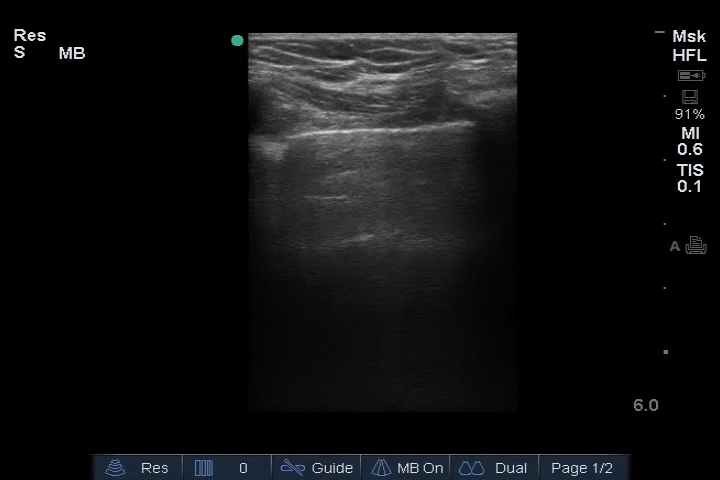

01_Lung_Ant_Right – Normal

02_Lung_Ant_Left – Normal